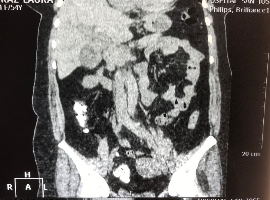

Citation: Ramos-FB, Gamboa LR, Rodriguez AE, et al. Gallbladder Adenocarcinoma Associated with Small Cell Tumor (Neuroendocrine), Collision Tumor, A Rare Case in the Literature and Review. Clin Image Case Rep J. 2021; 3(2): 138.